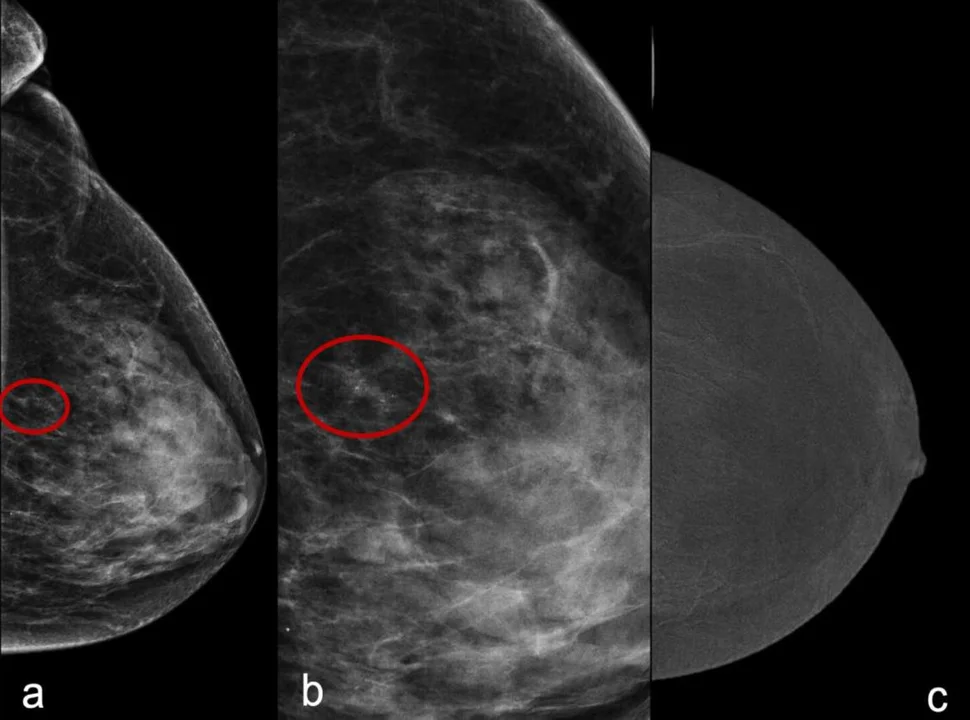

Mammografia to najbardziej czułe i bezpieczne badanie w profilaktyce raka piersi i najlepszy sposób, by wcześnie wykryć zmiany w piersi. Polega na prześwietleniu tkanek piersi promieniami rentgenowskimi. Pozwala znaleźć nieprawidłowości, zanim będzie je można wyczuć. W czasie badania wykonuje się dwa zdjęcia każdej piersi. Trwa ono kilka minut.